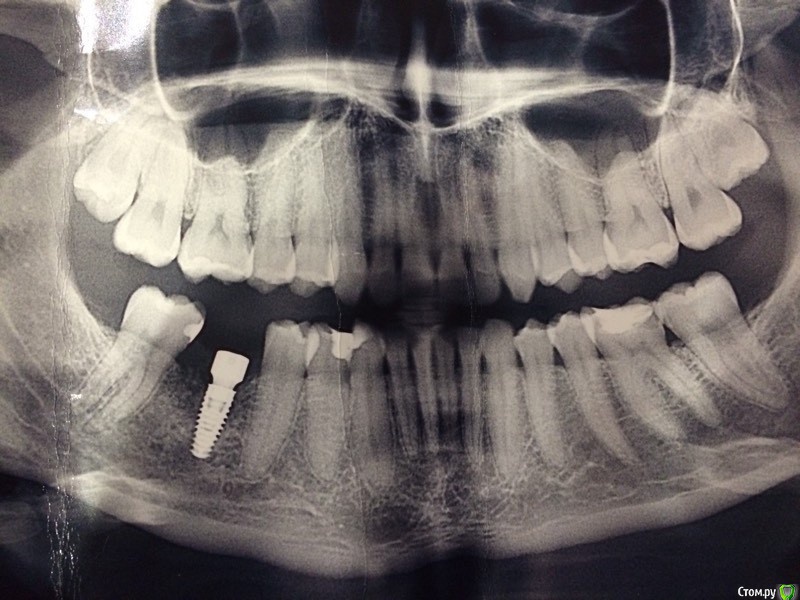

flyfli Опубликовано 23 апреля, 2018 Поделиться Опубликовано 23 апреля, 2018 Уважаемые доктора, подскажите мне ,пожалуйста, нужно ли что- то еще лечить из оставшихся зубов? Ссылка на комментарий

red_butler Опубликовано 24 апреля, 2018 Поделиться Опубликовано 24 апреля, 2018 я бы очно посмотрел зубы 3.6 3.7 И удалил бы восьмерки Ссылка на комментарий

flyfli Опубликовано 24 апреля, 2018 Автор Поделиться Опубликовано 24 апреля, 2018 Скажите, что Вы примерно видите на снимке с 6 кой??Сходила на консультацию один врач сказал: там кариес под пломбой и надо ставить вкладку циркониевую, второй врач сказал, что там киста дистальная у корня и что нужно вскрывать кломбу лечить канал и закрывать новой пломбой.Не знаю что и делать и что в конце концов с этим зубом.... Ссылка на комментарий

red_butler Опубликовано 24 апреля, 2018 Поделиться Опубликовано 24 апреля, 2018 Похоже на кариес на боковых поверхностях обоих зубов Ссылка на комментарий

flyfli Опубликовано 4 мая, 2018 Автор Поделиться Опубликовано 4 мая, 2018 подскажите,как быть на эту 6 ку лучше поставить пломбу или спилить все нафик и поставить коронку керамическую? Ссылка на комментарий

DmitrySH Опубликовано 5 мая, 2018 Поделиться Опубликовано 5 мая, 2018 подскажите,как быть на эту 6 ку лучше поставить пломбу или спилить все нафик и поставить коронку керамическую? Надо очно оценивать. может быть не коронку, а керамическую вкладку. Зависит от кол-ва оставшихся тканей зуба Ссылка на комментарий